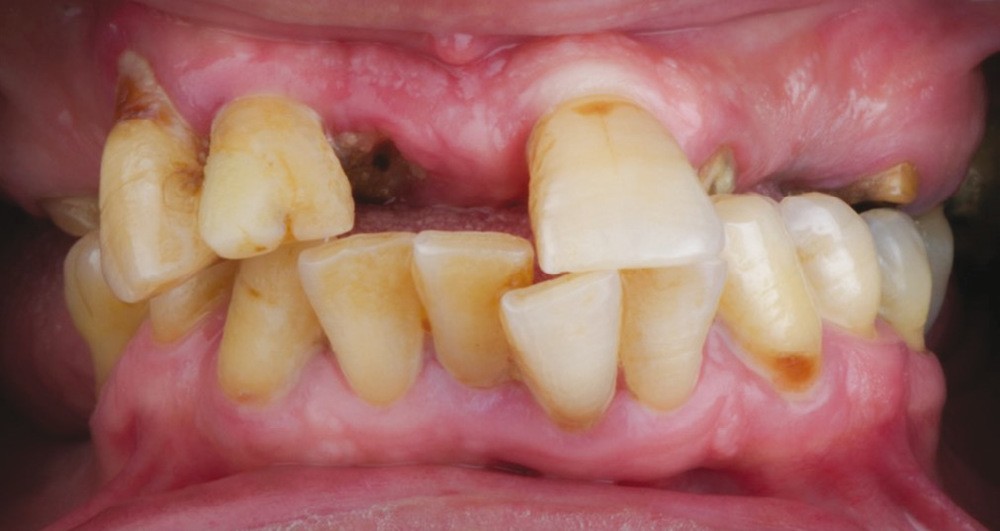

L’examen exobuccal montre une perte de dimension verticale d’occlusion (DVO) associée à un profil convexe et une biprochélie avec éversion de la lèvre inférieure (fig. 1).

À l’examen endobuccal, le sondage parodontal révèle une parodontite généralisée stade 4 grade A [1] caractérisée par des pertes d’attaches ≥ 5 mm, une alvéolyse au niveau radiographique > 50 % de la hauteur radiculaire, des pertes dentaires en raison de la maladie parodontale et des migrations secondaires dentaires.

L’analyse orthognatique crânio-faciale issue de la téléradiographie de profil confirme l’absence de décalage des bases osseuses (classe I squelettique), mais révèle une biproalvéolie aggravée par une forte vestibuloversion des dents antérieures conséquente aux pertes dentaires non compensées, à une déglutition dysfonctionnelle et à une hypotonie labiale.